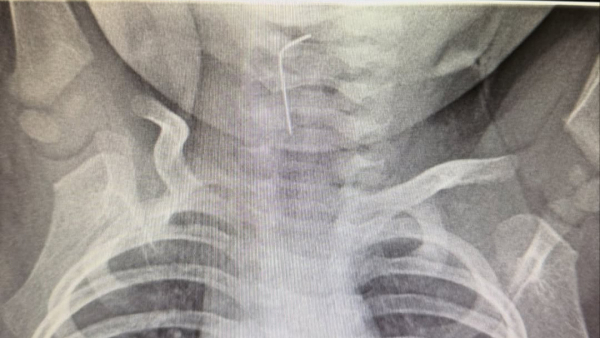

"Белгілі болғандай, сәби абайсызда ине жұтып қойған. Тез арада аурухана мамандары – хирург Темірбеков Мұхагали және эндоскопист Ырысқұлов Бабыр эндоскопиялық әдісті қолдана отырып, рентгенологиялық тексеру жүргізді. Нәтижесінде бөгде заттың нақты орналасқан орнын анықтап, өңеште тұрып қалған бөгде затты сәтті түрде алып шықты", – деп хабарлады Түркістан облысы әкімдігінің баспасөз қызметі.